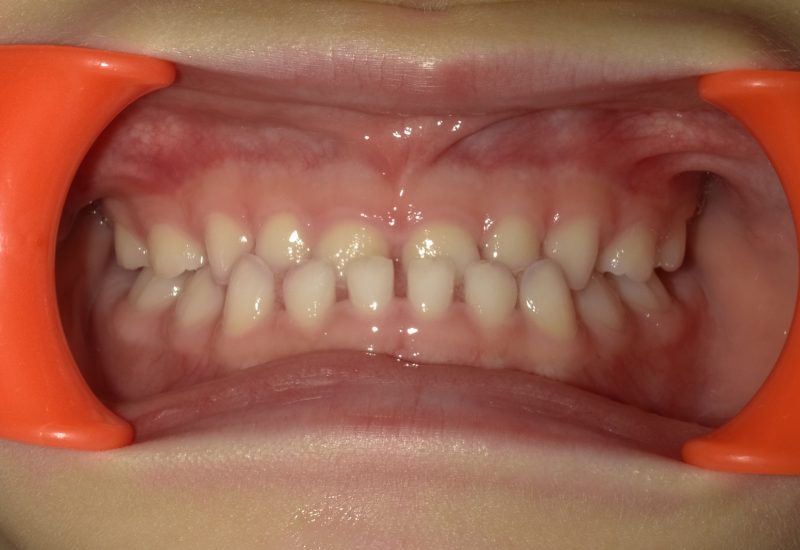

実際の乳歯列矯正治療の例です。前後反対だった前歯の咬み合わせが、正しい咬合に改善されています。